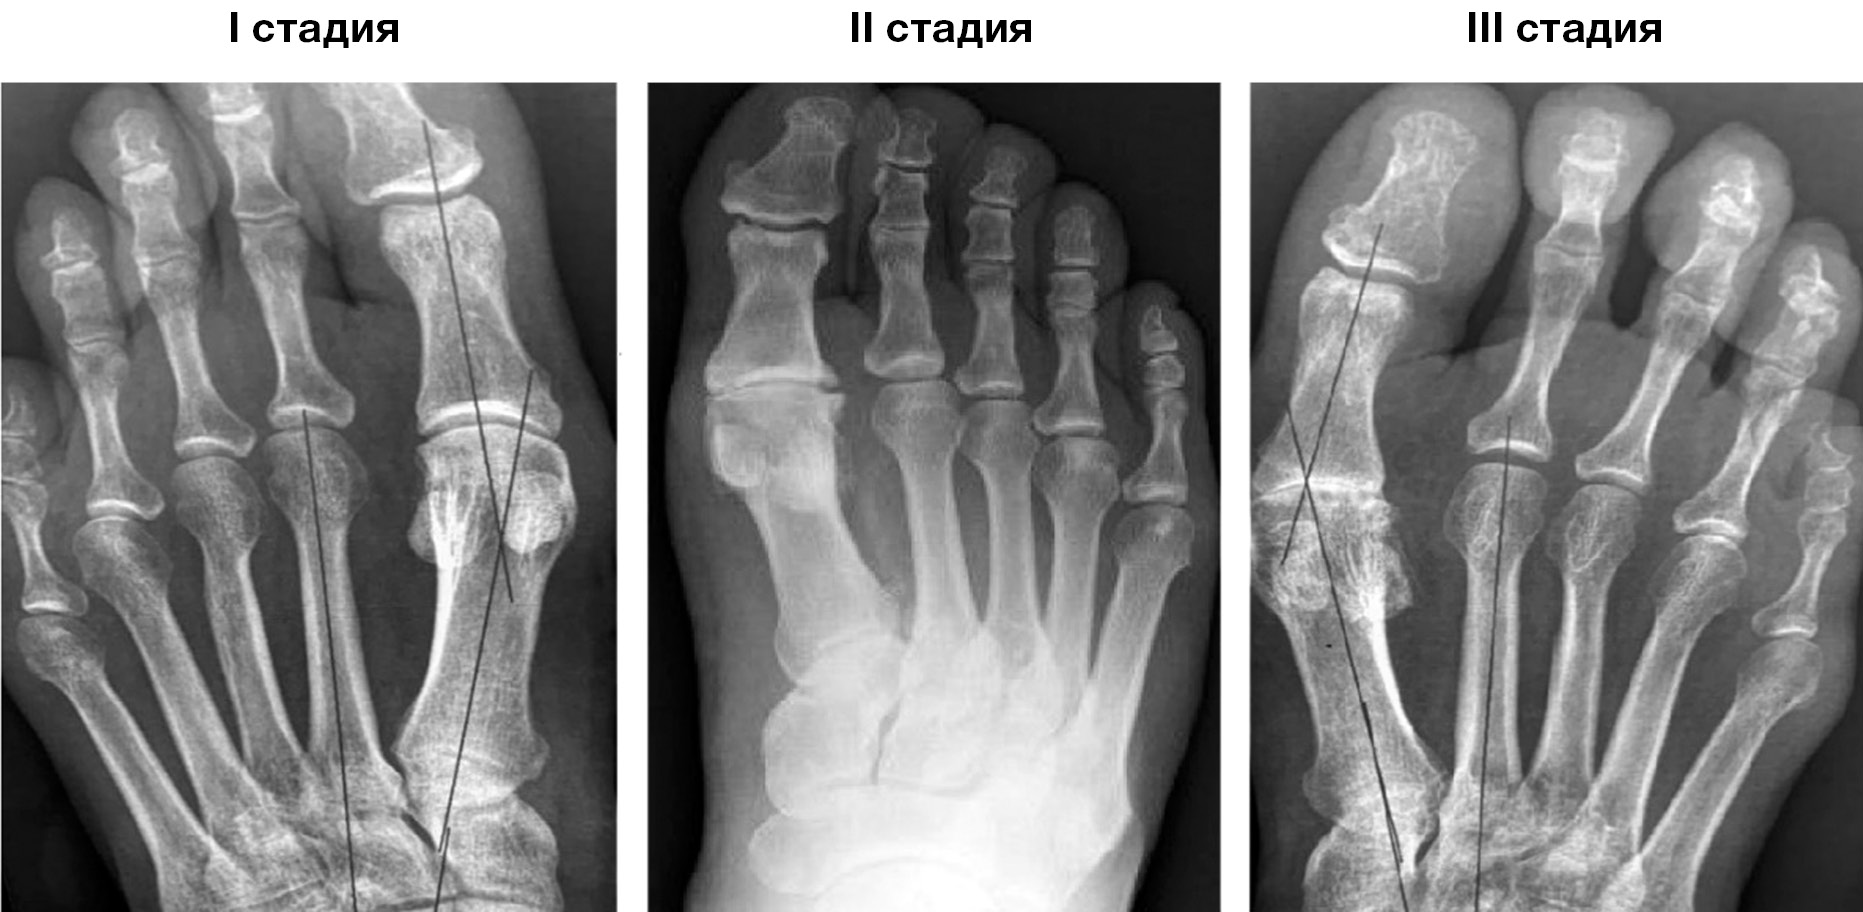

Рентгенологически выделяют три стадии заболевания (рис. 1).

Рис. 1. Рентгенологические стадии заболевания.

Fig. 1. X-ray criteria of 3 disease stages.